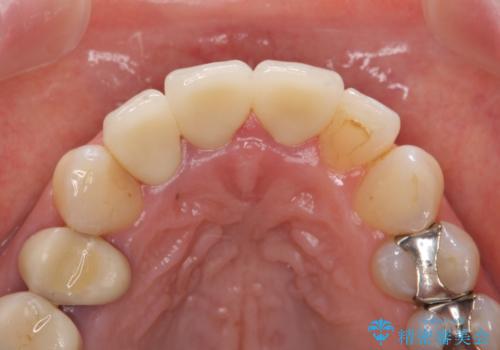

根尖病変を認めたため再根管治療を行った後、オールセラミッククラウン(スペシャル)にて補綴を行いました。

前歯の補綴ではオールセラミッククラウンを希望される患者様が多いですが、オールセラミッククラウンの中でも、エコノミー、スタンダード、スペシャル、エクセレントとランクがあります。

その中でも特に審美性が高いのがスペシャル、エクセレントです。スペシャル、エクセレントは口腔内写真をもとに熟練の技工士が、患者様の口腔内に合わせたオーダーメイドのクラウンを製作致します。